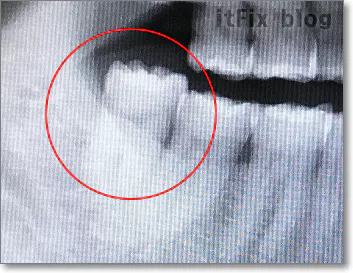

그래서, 가만히 내 사진을 보니 이랬습니다.

왼쪽 아래쪽 사랑니가 아파서 큰 맘먹고 수술도 각오하고 치과에 간 거였습니다. 위쪽 사랑니 양쪽 두 개는 오래전에 뽑아서 없습니다.

아직도 의문인 건 몇 년 전 치과에서는 이 사랑니를 보고 왜 큰 대학병원으로 가서 뽑아야 하며 수면마취를 해야 할지도 모른다고 했을까 하는 것입니다. 그동안 내 치아 사진을 휴대폰으로 찍어 두었더라면 내 상황에 대해 좀 더 올바른 판단을 했을 텐데 왜 보관해 두지 않았었는지 후회가 됩니다. 치과의사가 아닌 내가 봐도 이 정도라면 염증의 문제이지 치아의 문제가 아닌 듯 보이기 때문입니다.